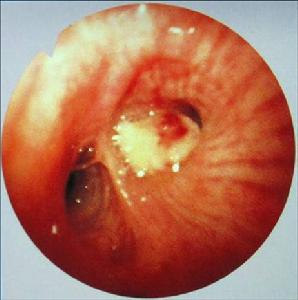

(一)中央型肺癌

發生在段支氣管以上至主支氣管的癌稱為中央型,約占3/4,以鱗狀上皮細胞癌和小細胞未分化癌較多見。

六、纖維支氣管鏡檢查

無對明確腫瘤的存在和獲取組織供組織學診斷均具有重要意義。對位於近端氣道內的腫瘤經纖支鏡刷檢結合鉗夾活檢陽性率為90%-